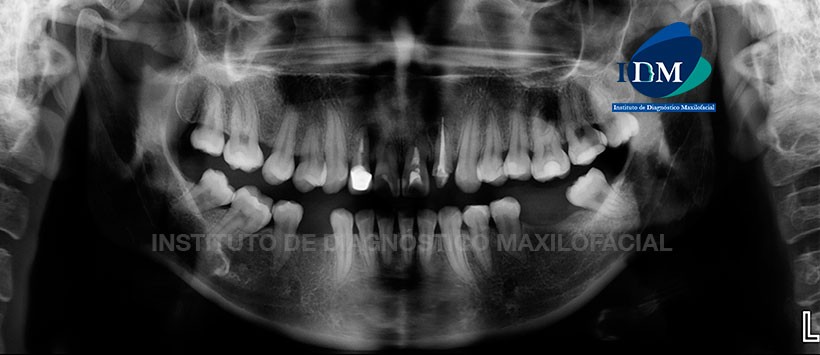

A la evaluación de la radiografía panorámica (Figura 1), evidenciamos un apiñamiento del sector dentario anterior, múltiples restauraciones, ausencia de algunas piezas dentarias.

Se evidencio en la pieza 12, corona protésica y presencia de material de obturación de conductos con proceso osteolitico en zona apical. En la pieza 21 material de obturación de conductos con perdida de continuidad del segmento radicular por mesial. Finalmente en la pieza 22 tallado coronario y material de obturación aparentemente sobreextendido con proceso osteolitico en zona apical.